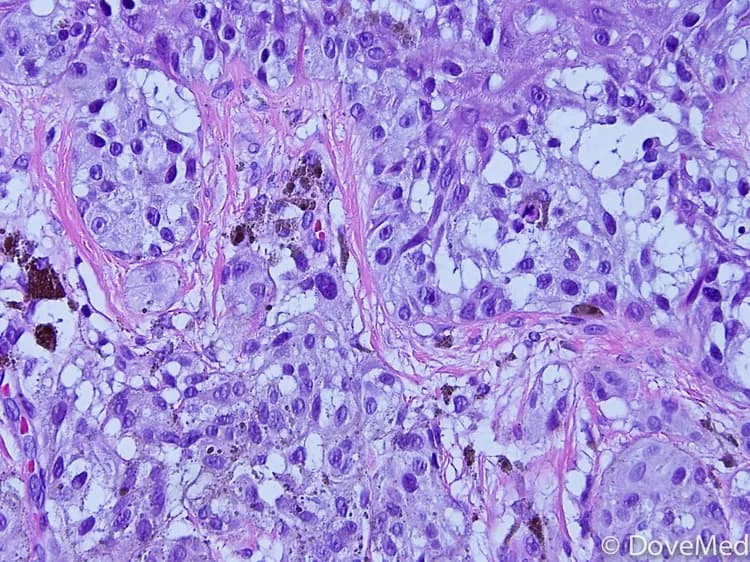

• A melanoma is a type of cancer that develops from cells, called melanocytes. Melanocytes are cells that produce melanin; the pigment that gives skin its color

• Although a less common form of skin cancer, it is far more dangerous and capable of spreading to other parts of the body. Melanomas that have spread to areas besides the skin are called Metastatic Melanomas